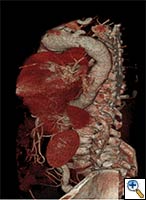

| FIGURE 1-3: 2D and 3D preoperative CT Images of a 78 year old man with aortic insufficiency, and ascending, arch and descending aortic aneurysm with mural thrombus. | |

Appropriate patients for this procedure have extensive thoracic aortic disease and a suitable landing zone for a stent graft in the descending aorta. Many of these patients are candidates for a 2-stage procedure, and selection is based on expected outcomes and the estimated interval rupture risk if patients were to be treated in a staged fashion. (see Figs. 1-3)

- Thorax CT angiogram with 3-D reconstruction, which is invaluable in the assessment of these patients. Attention must be paid to the detailed arch anatomy, taking note of any anomalies (eg. anomalous vertebral artery, bovine aortic arch), the diameter of the aorta distal to the LSCA, extent and diameter of the descending aorta aneurysm, and the diameter of the expected landing zone. Furthermore, the extent of atheroma/aortic calcification should be evaluated.